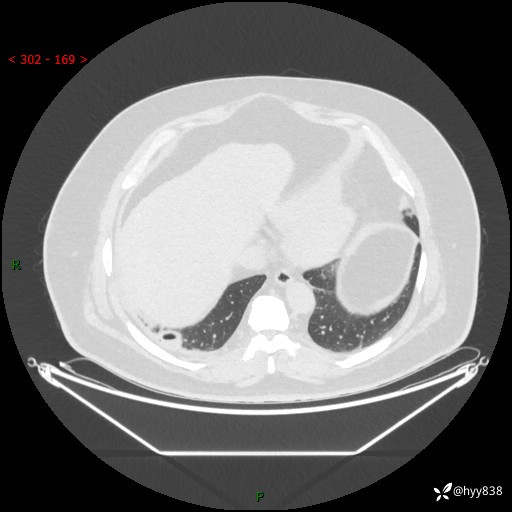

病例信息

性别:男

年龄:48岁

简要病史:发热来诊(门诊病人)

胸部CT平扫